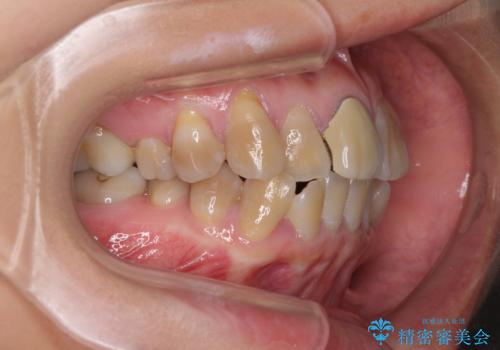

- 八重歯や前歯のデコボコを気にして来院された患者様です。

歯列が前方に傾斜しており、デコボコが強かったため、上下左右第一小臼歯4歯を抜去し、ワイヤー装置による矯正治療を行うこととしました。

上下の正中がずれていましたが、抜歯矯正であったので、極力正中位置を合わせるように治療を進めて行きました。

顎間ゴムの使用などにより、正中位置を改善することができました。